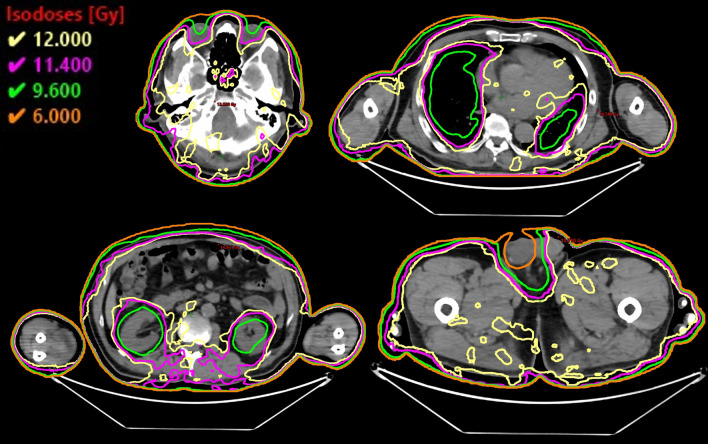

The DVH parameters are summarized in Table 2 and Fig. 3. Figure 4 shows the dose distributions. The Dmax of the whole body was 15.7 Gy (130%). The PTV D98%, D95%, D50%, and D2% were 8.9 Gy (74.2%), 10.1 Gy (84.2%), 12.6 Gy (105%), and 14.2 Gy (118%), respectively. The HI was 0.42. In terms of OARs, the Dmean of the lungs, kidneys, lens, and testes were 9.6 Gy, 8.5 Gy, 8.9 Gy, and 4.4 Gy, respectively. The Dmax of the testes was 5.8 Gy. The V12Gy of the lungs and kidneys were 4.5% and 0%, respectively. The V5Gy of the lungs was 100%. The DVH parameters met our goal for the target and almost all OARs, except for the V12Gy of the lungs (Table 2). Additionally, the total MU was 8996.

Fig. 3.

Dose-volume histograms of the planning target volume (PTV), lungs, kidneys, lens, and testes. The Dmax of the whole body was 15.7 Gy (130%)

Fig. 4.

Dose distributions of different computed tomography slices, including the lens, lungs, kidneys, and testes. Yellow line, 12 Gy (100%) iso-dose line; magenta line, 11.4 Gy (80%) iso-dose line; green line, 9.6 Gy (80%) iso-dose line; orange line, 6.0 Gy (50%) iso-dose line